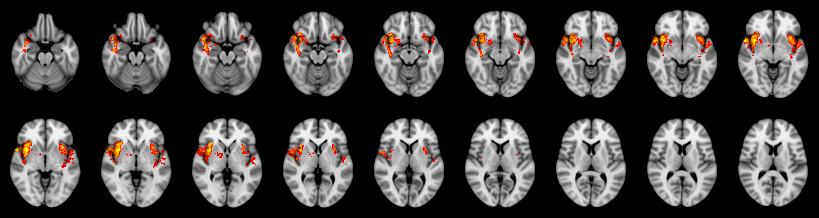

Pain study, TFCE, Corrected

Combined

Tippett:

Fisher:

Stouffer:

Edgington:

Mudholkar–George:

Friston:

IUT/Conjunction/Nichols:

Hotelling T2: